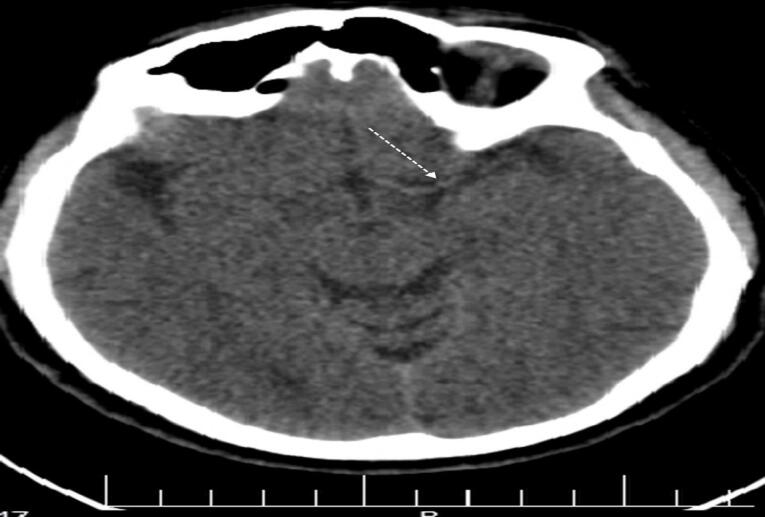

急性脑血栓性中风后,毒蛇咬伤是一种罕见的发生。有一些记录的病例脑梗死导致各种毒蛇种类的毒害。然而,这些报道中都没有特别详细的由大毒蛇中毒或血管闭塞引起的卒中而没有并发脑梗死的病例。在这项研究中,我们提出了一个病例的大脑中动脉(MCA)闭塞在一个56岁的男子谁是咬大毒蛇或毒蛇lebetina。这个人的右脚被蛇咬伤,导致随后的癫痫发作和意识丧失。脑部非对比计算机断层扫描显示右侧MCA高衰减,表明动脉内血栓闭塞,通常称为MCA高密度征或Gács征。

Acute cerebral thrombotic stroke following a viper snakebite is a rare occurrence. There have been a few documented cases of cerebral infarctions resulting from envenomation by various viper species. However, none of these reports have specifically detailed instances of stroke induced by Macrovipera lebetina envenomation or vessel occlusion without concurrent cerebral infarction. In this study, we present a case of middle cerebral artery (MCA) occlusion in a 56-year-old man who was bitten by a Macrovipera or Vipera lebetina snake. The individual experienced a snakebite on his right foot, leading to subsequent seizure activity and loss of consciousness. Non-contrast computed tomography scan of the brain revealed hyperattenuation of the right MCA, indicating clot occlusion within the artery, commonly referred to as hyperdense MCA sign or Gács sign.